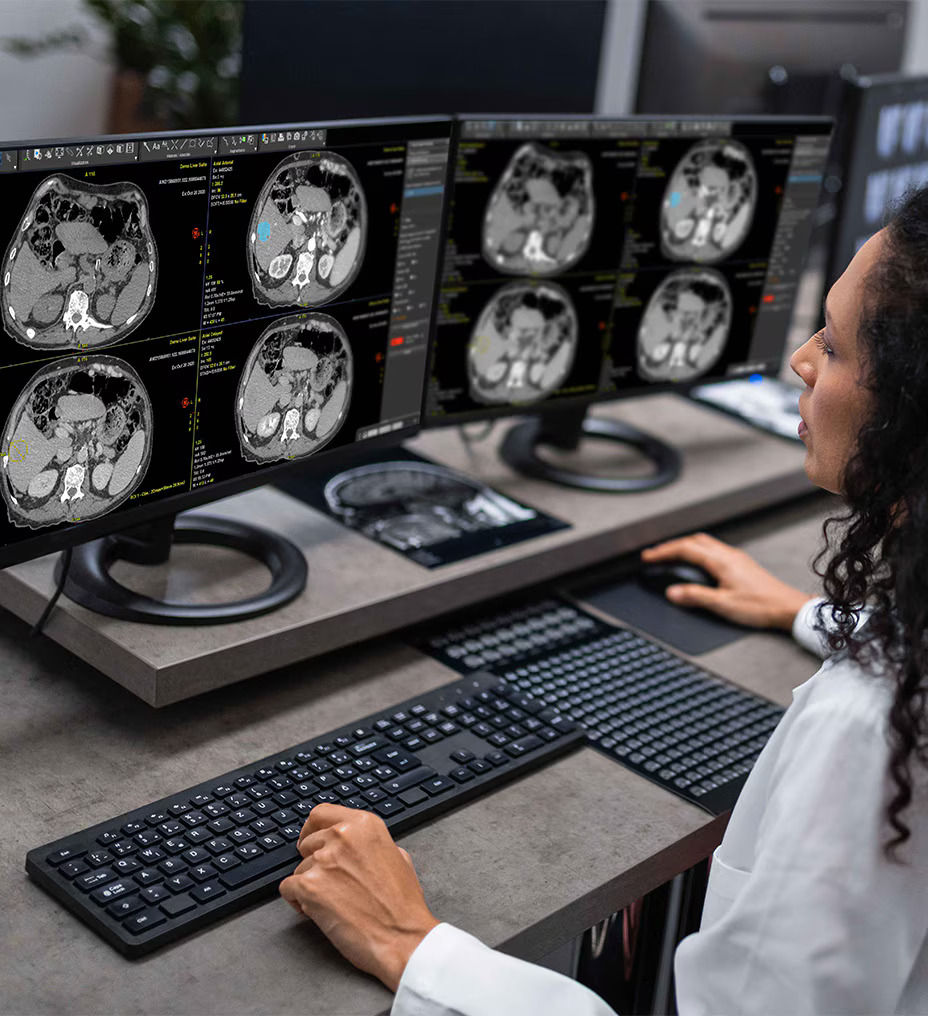

Streamlines the review and reporting of multi-phase CT liver exams for patients with known or suspected hepatocellular carcinoma (HCC).

Liver Suite provides a guided workflow that can be used as a standalone protocol within Volume Viewer or as part of Hepatic VCAR¹ liver assessment on CT multi-phase data.

The application reduces the time it takes to calculate an LI-RADS score, giving you the ability to inform more suspected HCC cases. Automatic hepatic phase identification and registration of series centered on the liver along with semi-automatic contouring of observations with an auto contour tool save you time. AI technology² assists with the extraction of LI-RADS v2018 major features (APHE, washout, capsule).